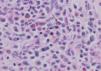

Se realizó una biopsia de una lesión de la mama y de otra del cuero cabelludo. En ambas lesiones el estudio anatomopatológico fue similar, con la presencia de un denso infiltrado en dermis reticular compuesto por células mieloides en diferentes estadios de maduración y por megacariocitos. Se practicó un estudio inmunohistoquímico, observándose positividad para la mieloperoxidasa y para el CD68. El número de células CD34 positivas no fue significativo. Estos hallazgos fueron compatibles con el nuestro de hematopoyesis extramedular cutánea (figs. 3, 4 y 5).

Histológicamente se caracteriza por un infiltrado dérmico de aspecto polimorfo, compuesto por una combinación de precursores mieloides, eritroides y megacariocitos13. En una revisión de casos de hematopoyesis extramedular cutánea, realizada por Mizoguchi et al10, encontraron que en un número elevado de casos sólo existían precursores de dos o de una serie hematopoyética. En los niños con frecuencia existe un predominio de los precursores eritroides, y los megacariocitos suelen estar ausentes, mientras que en los adultos suelen predominar los megacariocitos2. Sólo la mitad de los casos con hematopoyesis extramedular cutánea en adultos muestran precursores eritroides en la biopsia2. A través de estudios inmunohistoquímicos se han observado reacciones positivas para mieloperoxidasa (serie mieloide) y para el factor de von Willebrand (serie megacariocítica). La mayoría de células precursoras mieloides eran únicamente positivas para mieloperoxidasa, confirmando su estirpe granulocítica. Sólo en una minoría de células se observó positividad para el CD68, el cual es expresado tanto en células granulocíticas maduras e inmaduras como en monocitos y macrófagos16. En un caso publicado por Kwon et al se observó un gran número de precursores eosinofílicos, siendo su significado desconocido hasta el momento11.